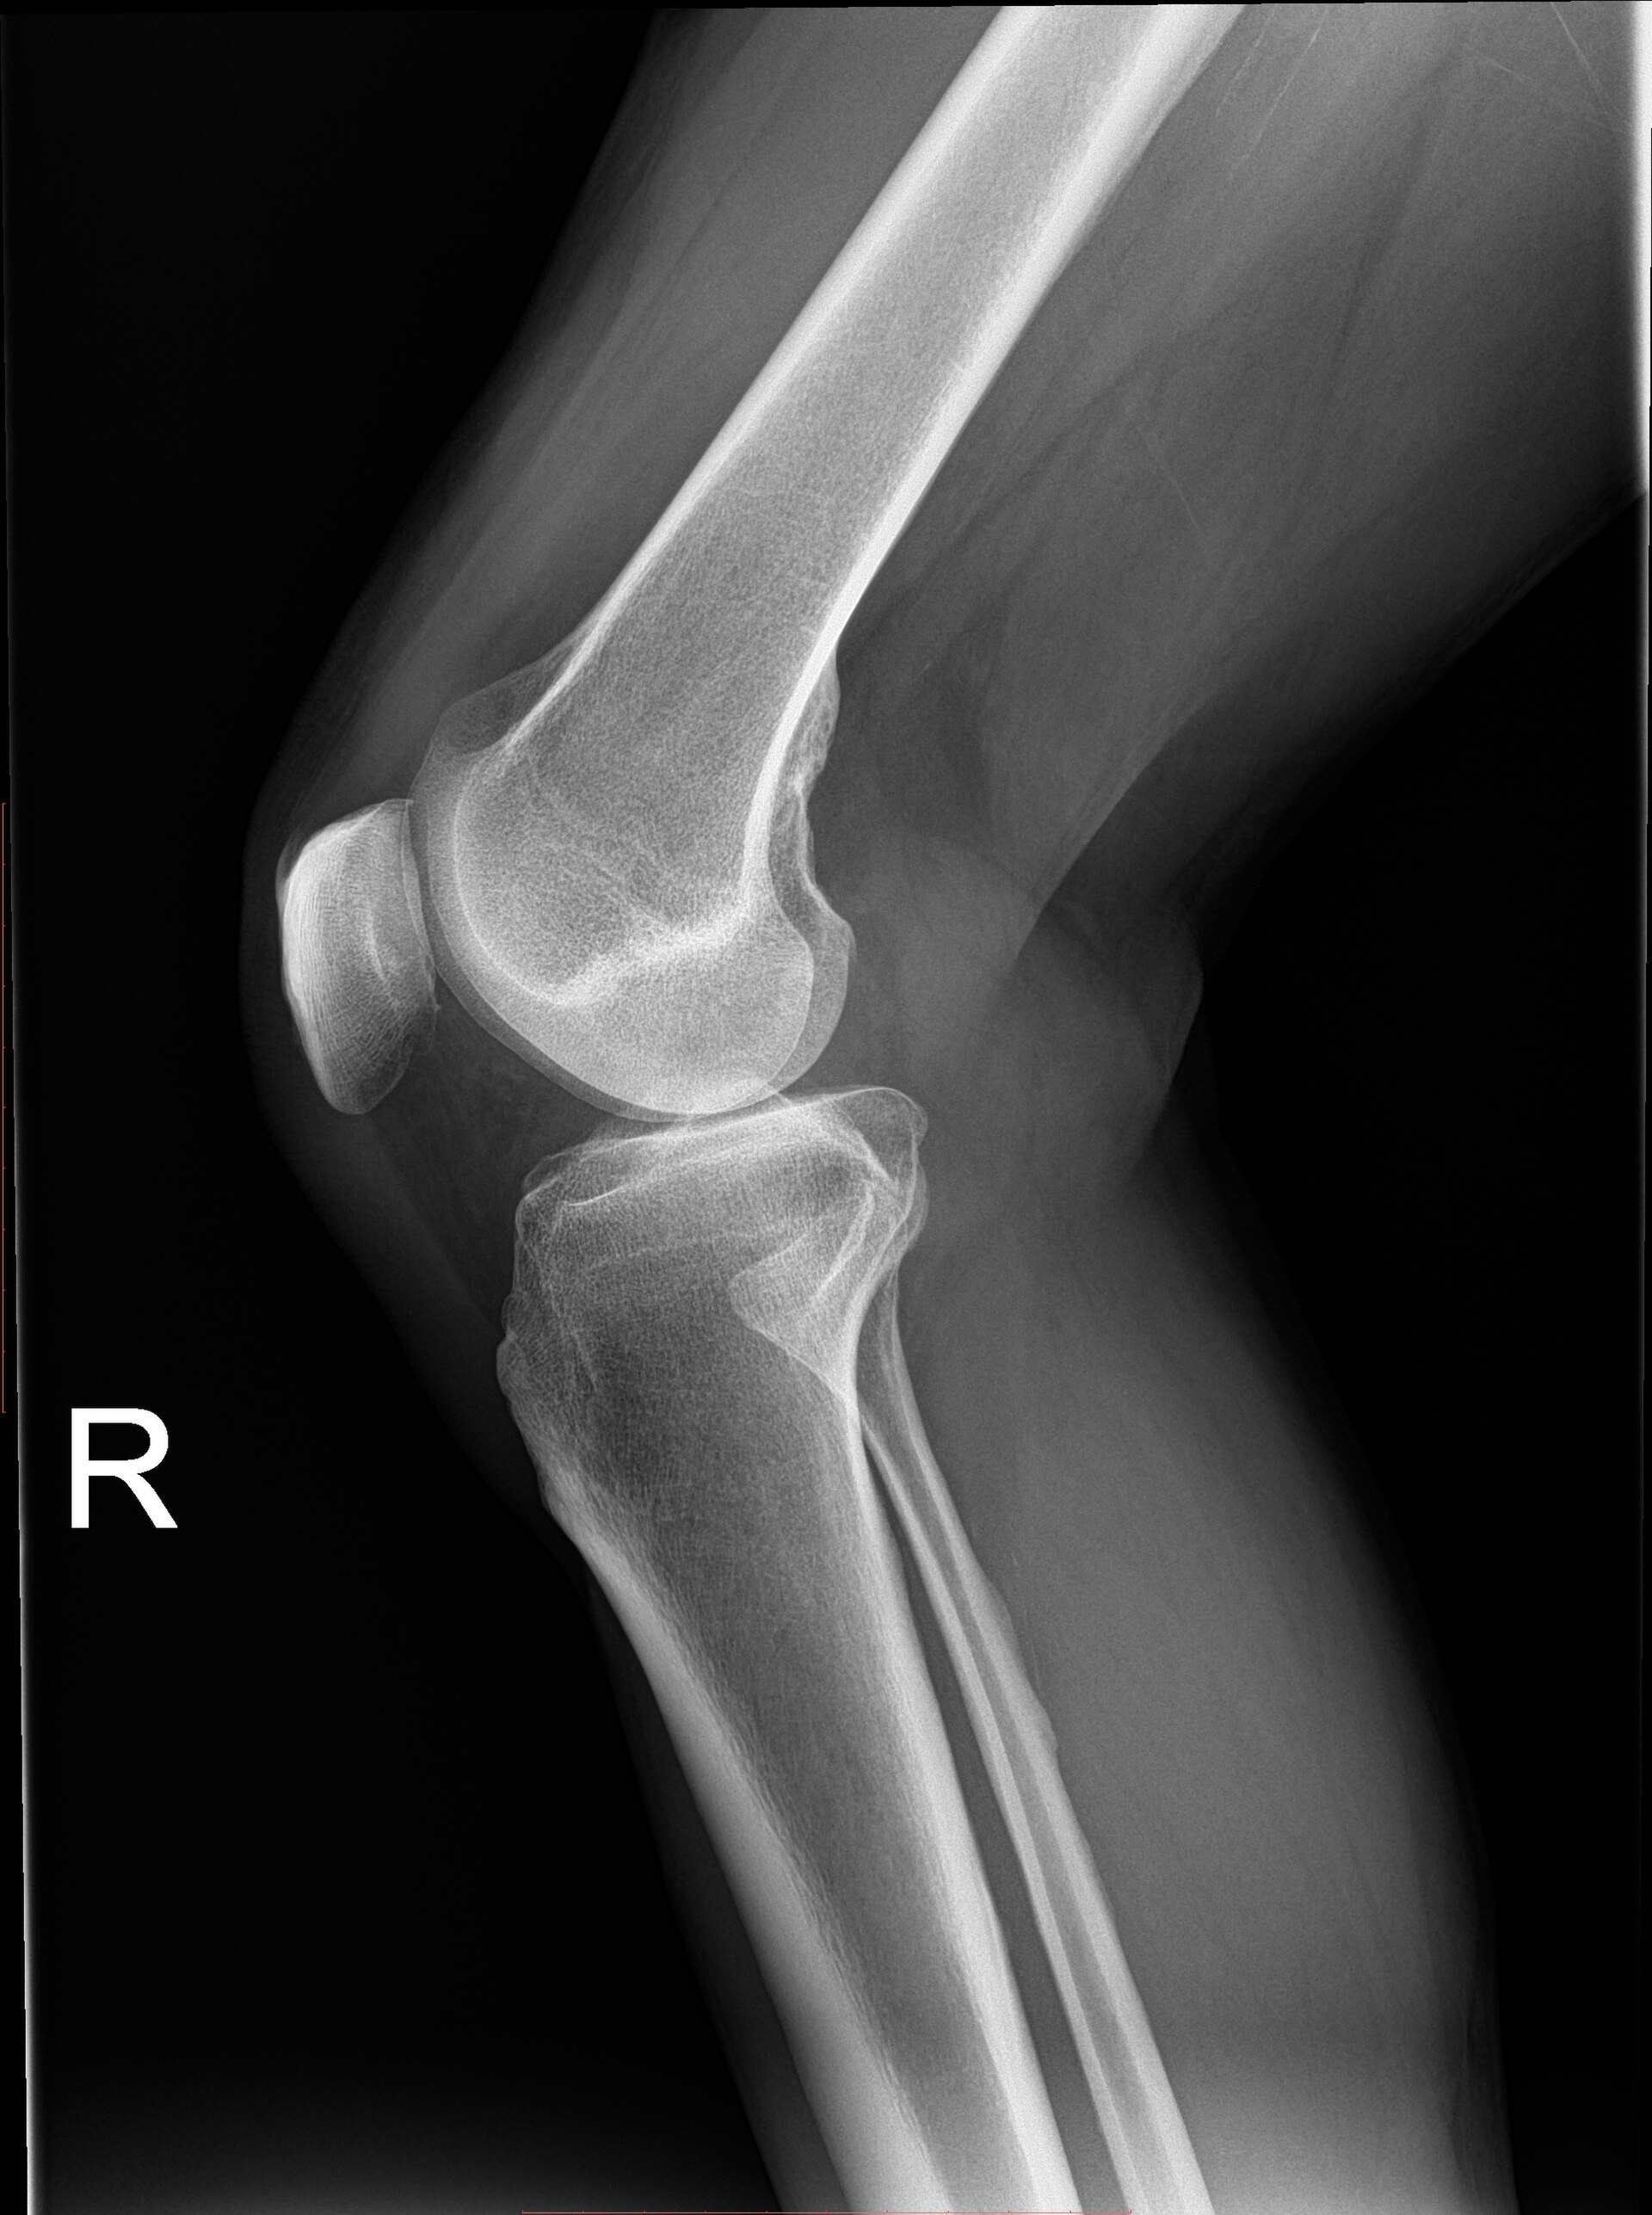

Plain radiograph of a human knee joint showing the femur, tibia, and patella.